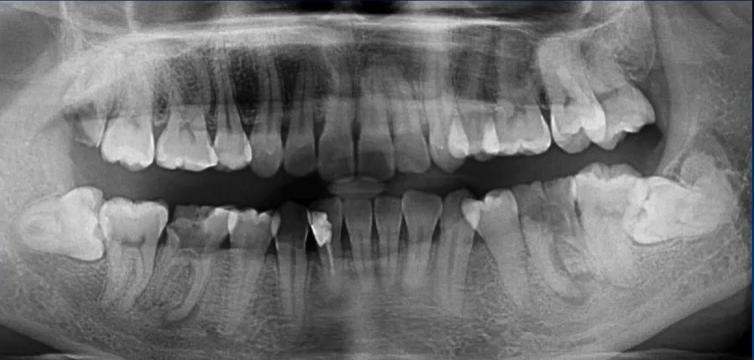

一、理想曲断影像

中线左右对称,牙齿排列呈微笑弧形,片子左右两边相对对称,能清晰显示颞下颌关节、上下牙列的牙根,图像的对比度和分辨率较好。

1. 全面显示牙列:牙体疾病初步诊断

比如下面这张片子显示出的龋坏合并根尖周炎。

2. 混合牙列期:乳牙情况、恒牙胚观察

曲面断层片拍摄时体位相对比较简单,小患者的配合程度相对高一些。

因为曲面断层片反映的是上下颌牙齿、上颌窦、关节,在一张片子中所展示的解剖结构较多。比如刚才的片子,最容易诊断的是右下6远中邻面深龋合并根尖周炎,左下有埋伏的多生智齿,右侧是垂直智齿。

注意不要遗漏,比如片子中显示上颌两个3是缺失的,是先天性缺失还是做过手术?有可能会漏掉一些临床信息。